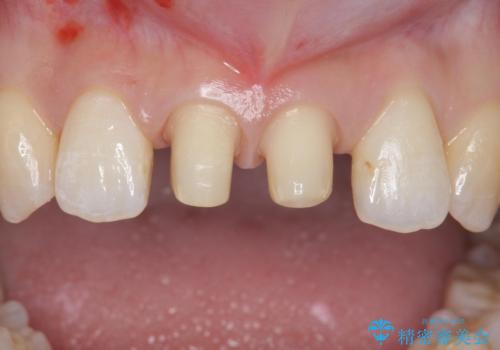

マウスピース矯正を行った後、かぶせ物で審美性を改善していきます。

前歯には審美性も適合も良いクラウンを装着。

歯ぐきの状態も非常に良いです。